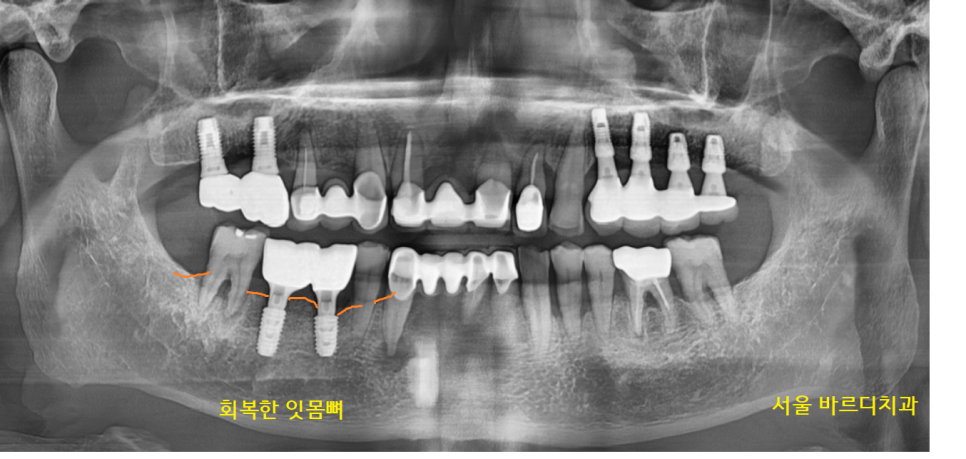

23.10.26

명일역 임플란트 수술 후 사진입니다.

심었던 임플란트도 관리가 제대로 안되면

잇몸뼈가 녹아서 오래 못쓰는데요.

움직이는 치아 관리와 함께

명일역 치과에서

계속적으로 관리해드릴게요~!!

23.11.09

수술 후 관리

임플란트와 보철 2년까지 보장해 드리고 있습니다.